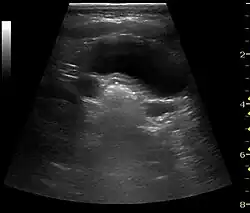

With US, larger stones (>5–7 mm) within the kidney, i.e., in the calyces, the pelvis and the pyeloureteric junction, can be differentiated, especially in the cases with accompanying hydronephrosis (Figure 18 and Figure 19). Hyperechoic stones are seen with accompanying posterior shadowing. Additional twinkling artifacts below the stone can often be seen using Doppler US. Large stones filling the entire collecting system are called coral stones or staghorn calculi and are easily visualized with US (Figure 20). Stones in the ureters are usually not visualized with US due to the air-filled intestines obscuring the insonation window. However, ureteral stones near the ostium can be visualized with a scan position over the bladder. An exam of the ureteric orifices and the excretion of urine to the bladder can be performed by inspecting the ureteric jets in the bladder with color Doppler US.

Figure 19. Centrally located stone with posterior shadowing. No hydronephrosis is present. Measurement of kidney length on the US image is illustrated by '+' and a dashed line.[1]